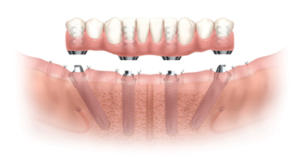

Stamford Periodontics and Implant Dentistry Center offers edentulous patients an efficient and effective restoration using only four implants to support an immediately loaded full-arch prosthesis.

Stability even in minimum bone volume

By tilting the two posterior implants, longer implants can be used in minimum bone volume, increasing bone-to-implant contact and reducing the need for vertical bone augmentation. The tilted posterior implants can be anchored in better quality anterior bone, reducing cantilevers and thus improving support of the prosthesis.